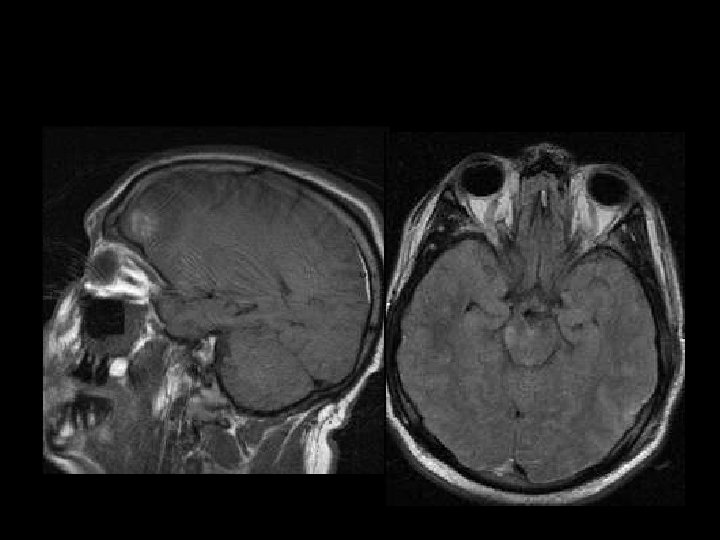

DIFFUSE AXONAL INJURY n Jarang terdeteksi pada CT ( 20% dari lesi DAI berupa perdarahan) n MRI: T 1, T 2 GRE, SWI

Sagittal T 1 -W images

Axial FLAIR images